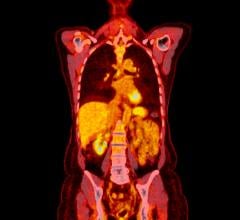

The study will use a cost-effective, risk-diluted approach for rapid development and testing of molecularly-targeted imaging agents in phase 0 microdosing studies. The microdosing studies are designed to evaluate imaging of specific targets.

“Targeting an evaluation of imaging in early human surgical trials will allow us to efficiently assess potential candidates for further development,” said Brian Pogue, Ph.D., lead investigator and Dartmouth professor. “This approach will dramatically accelerate the paradigm shift to molecularly guided surgical oncology. This grant will allow us to develop and test agents produced with current Good Manufacturing Practices whose primary use will be in diagnostic guidance in surgical oncology, and used at microdoses similar to nuclear medicine tracers.”

The first agent will be an Affibody molecule targeted to the epidermal growth factor receptor (EGFR), which is overexpressed in a broad range of cancers.

The study will employ commercially available state-of-the-art surgical microscopes from Leica and Zeiss that are equipped for intraoperative fluorescence imaging. Surgical signal detection and binding specificity will be the primary outcomes from the phase 0 trials. First-in-human studies with recurrent high-grade brain tumor patients will be pursued at Dartmouth. Approval for the microdosing studies will be sought under the exploratory investigational new drug (IND) pathway at the FDA.